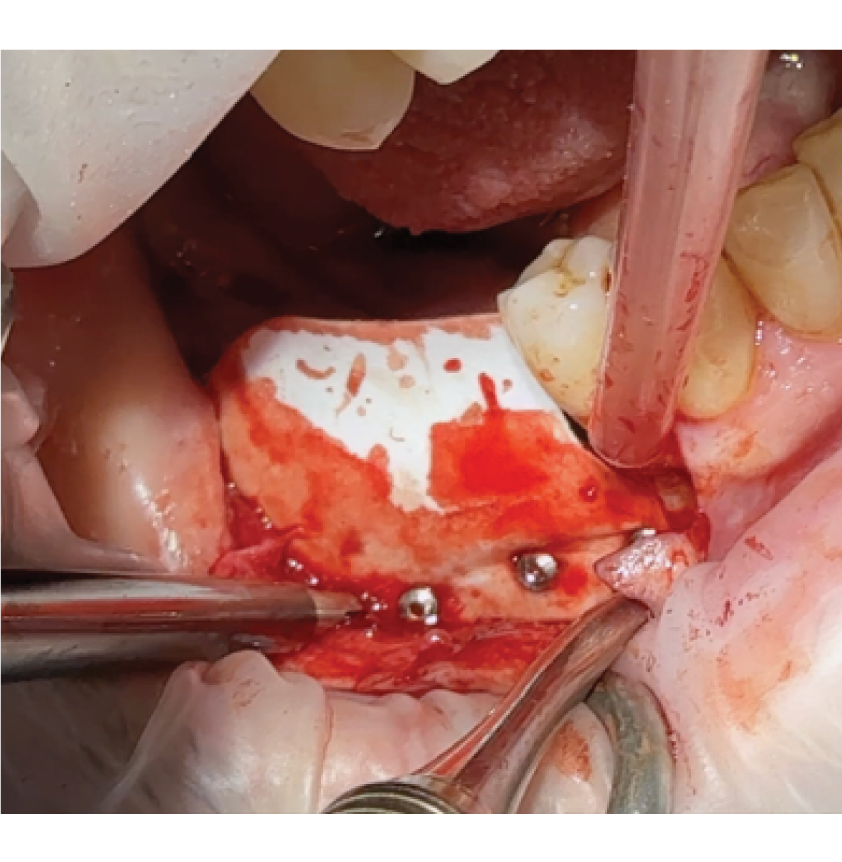

Director’s Clinical Cases

Director’s Clinical Cases